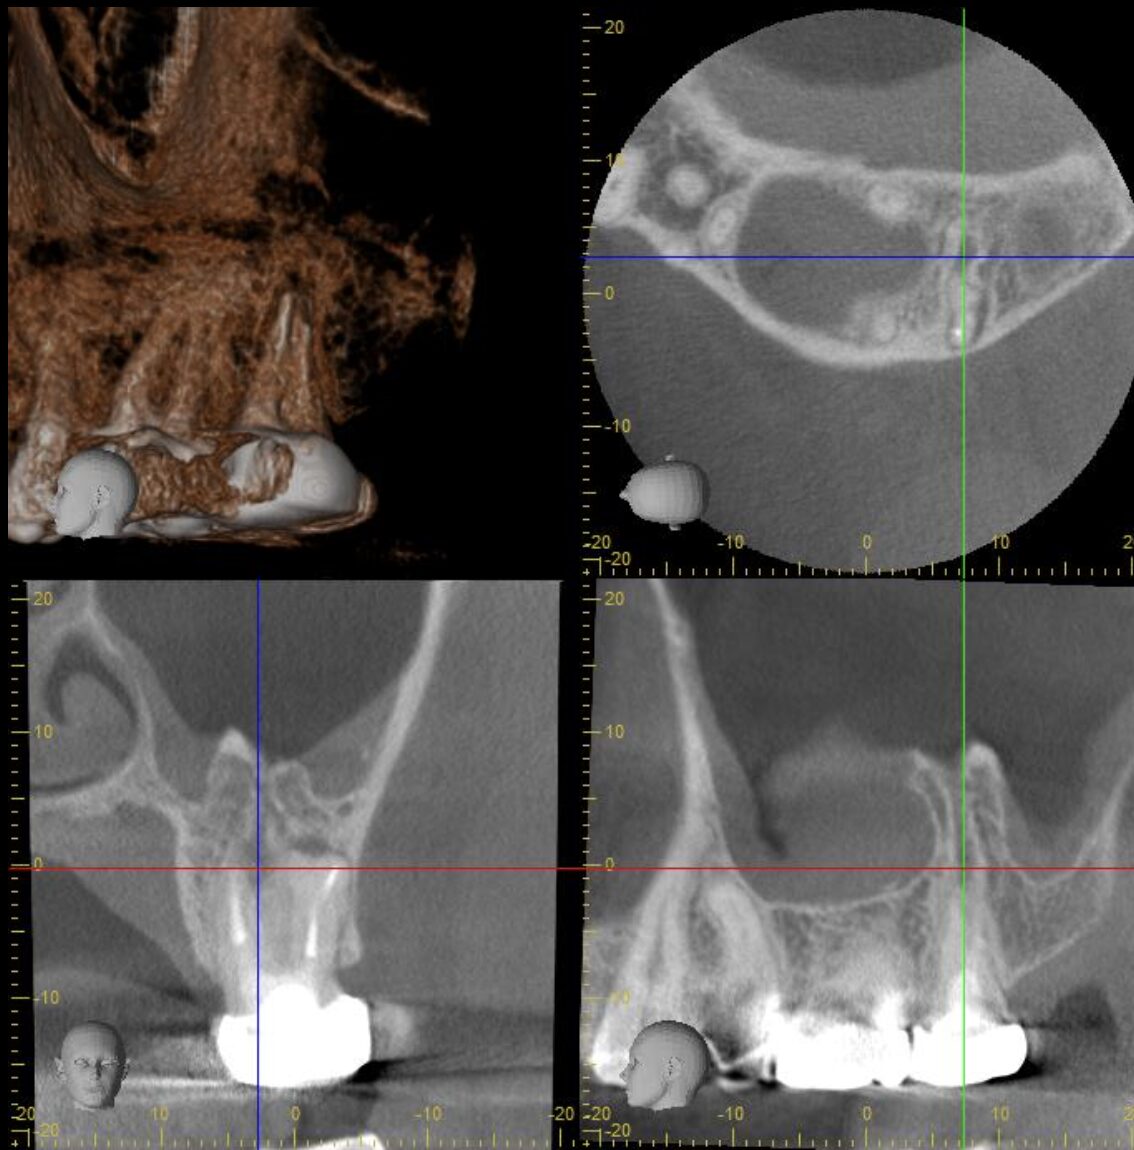

再治療(イレギュラーかつ見逃された根管)

- 主訴

- 以前に神経を抜いた。最近、その歯が痛くて噛めない

- 治療内容

- 左上第二大臼歯

口腔内診査とCTから、根尖性歯周炎と診断。根管治療の再治療が必要です。

CTの所見では、根尖周囲の病変は大きく成長し、上顎洞粘膜を持ち上げ、さらに上顎洞粘膜の肥厚も認めます。病変と上顎洞は一部交通している状態。

治療をスタートしてみると、根管内は著しく感染していました。

また、見逃された根管を認めました。

根の中は、形、本数、位置に個人差があり、全く同じ構造の歯はほとんどありません。

前医での治療に不備があったというよりも、今回のようにイレギュラーな位置での根管は、マイクロスコープやCTや専門器具がないと、発見することが不可能なことが多いです。

また、イレギュラーな根管を持つ歯は、分岐の位置や根の形もイレギュラーなことが多く、さらに隠れた道がないかを探索し、それらを拡大、洗浄する必要がありました。

根尖孔が大きく開いていたので、その部分はMTAセメントで封鎖し、他の部分はガッタパーチャーで根管充填を行いました。

術後3ヶ月のCTで、治癒が認められました。

- 治療期間

- 3回

- 治療のリスク

- 今回のような、複雑な形の根管を有する歯は、見逃した根管を見つけることができたとしても、器具が届かないエリアが存在することも多く、根管治療だけで治癒ができない場合があります。

もし、治癒が期待できない場合は、意図的再植術という処置へ移行することを話し合いました。

BEFORE

AFTER